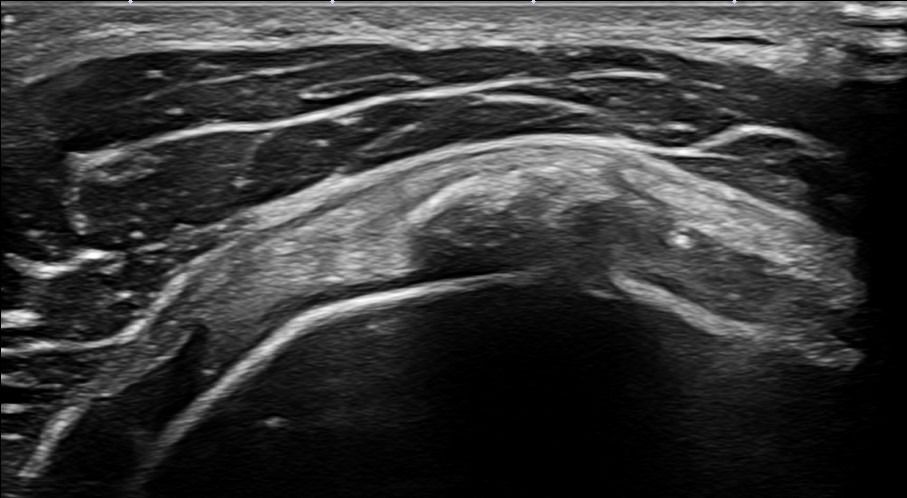

- Ρήξη των τενόντων (υποπλάτιος, υπερακάνθιος, υπακάνθιος και ελάσσων στρόγγυλος τένοντας)

Επιπλέον, το Υπερηχογράφημα Ώμου μπορεί να διαγνώσει τενοντοπάθεια, τενοντοελυτρίτιδα ή ρήξη στον τένοντα της μακράς κεφαλής δικέφαλου βραχιονίου.